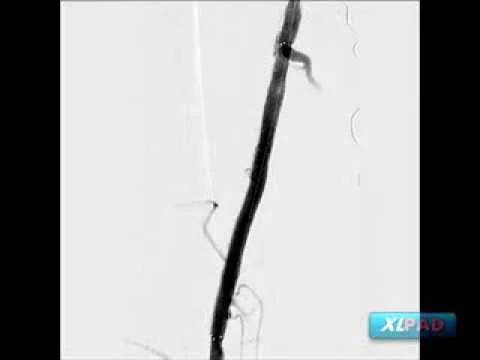

Viance to Cross CTO with Atherectomy